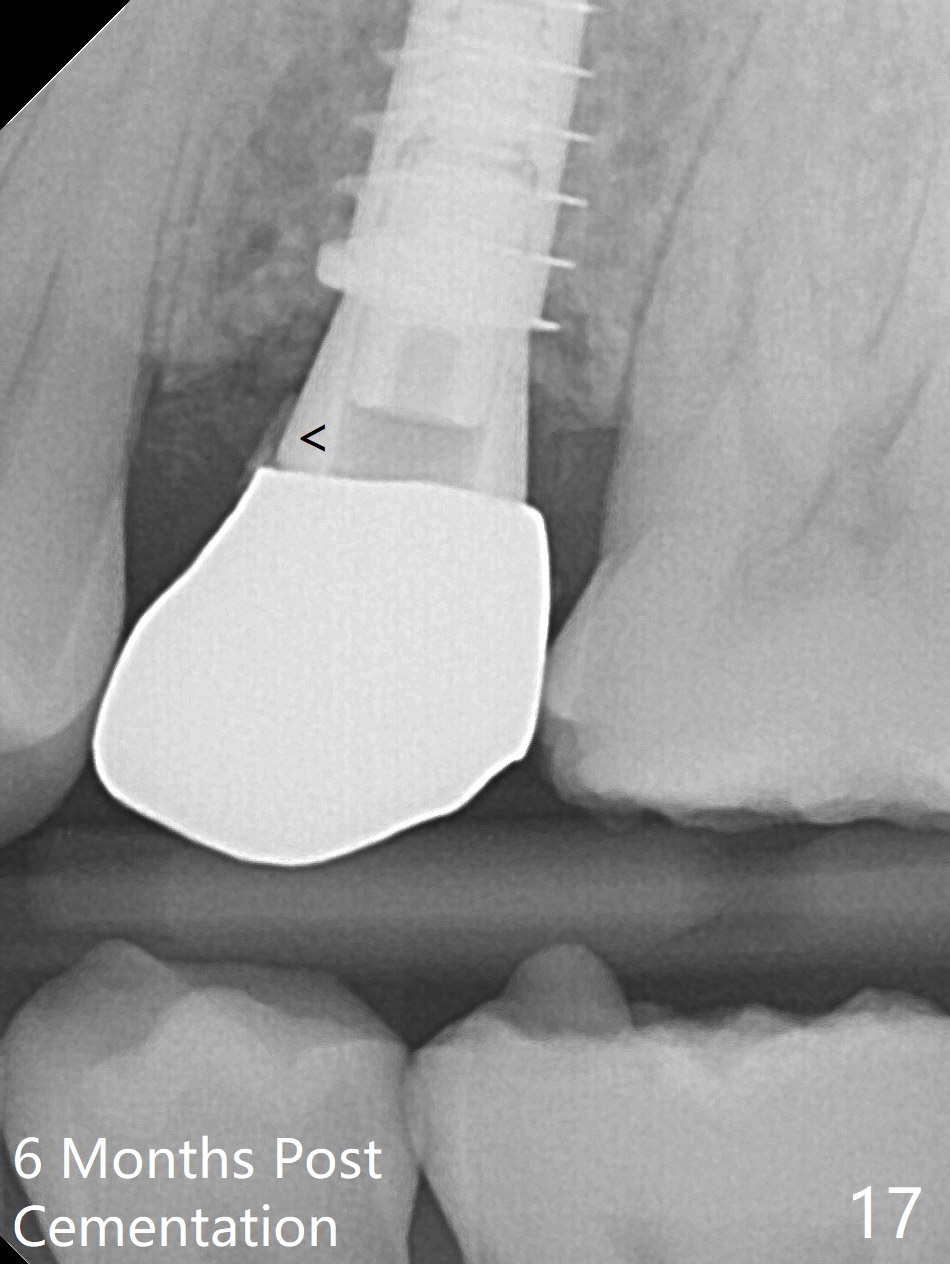

The buccal gingival inflammation subsides 1 week postop (Fig.13,14). There is no bone loss 4 months postop (Fig.15,16). The crown is recemented 6 months post cementation (probably due to short abutment); there is a residual cement (Fig.17 <), which is removed (Fig.18).